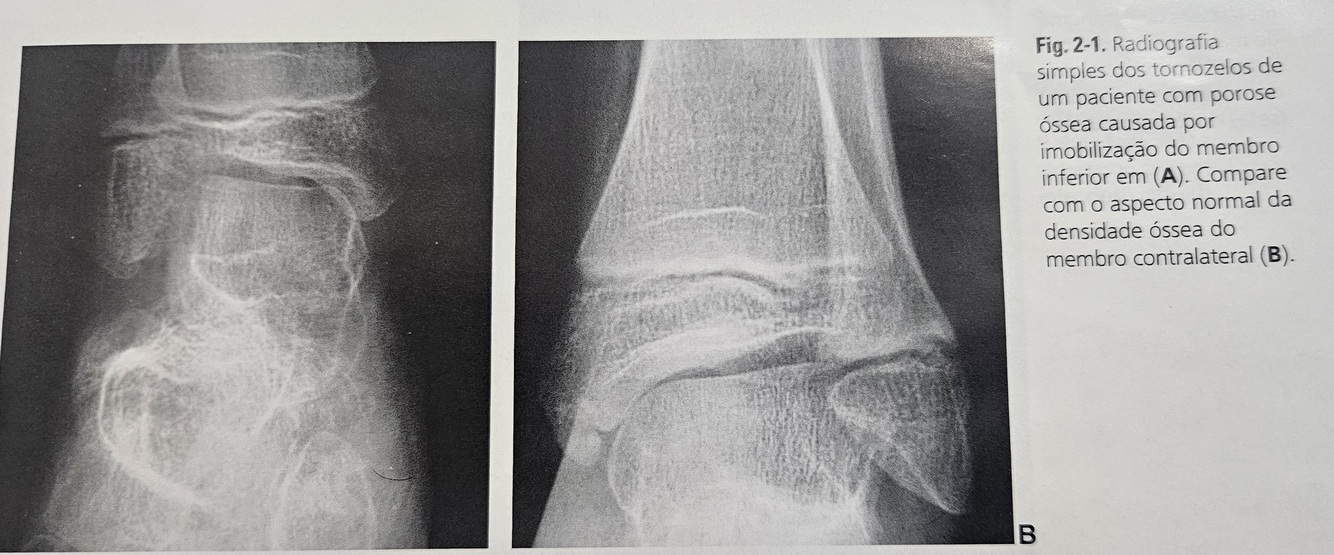

O que seria POROSE e como se apresenta na radiografia?

Porose está relacionado com perda de massa osse por desmineralização.

Se apresenta mais radiotransparente que um osso com mineralização normal.